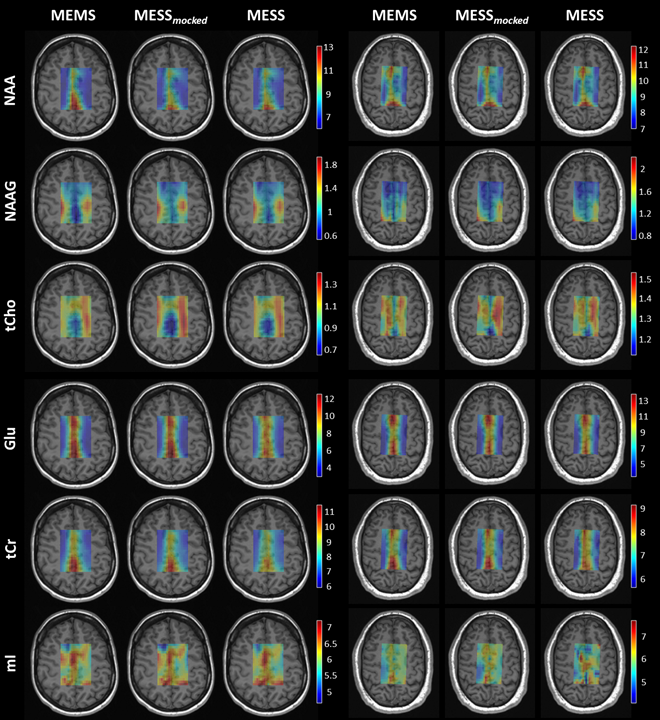

A comparison of concentration and T2 maps across two volunteers is reported in Fig.3 and Fig.4 for a subset of metabolites. MESS-mocked replicates MEMS adequately, thus signal truncation is found suitable for concentration and T2 mapping. MESS yields maps that overall agree with the 3-fold slower MEMS technique here considered the gold standard for comparison. The distribution of concentrations and T2s between GM and WM is reported in general agreement with the literature.13,15–19

Fig.4: T2 maps in millisecond units [ms] of parenchymal water and a subset of metabolites, reported for two subjects and the three methodologies. H2O: parenchymal water, tCho-CH3: total choline singlet at 3.2ppm, NAA: N-acetylaspartate singlet at 2ppm, mI: myo-Inositol, tCr-CH2: total creatine methylene resonance at 3.9ppm and tCr-CH3: tCr methyl resonance at 3ppm. Maps are displayed with zero-filling in spatial domain with cropped voxels at the edges (20x20 voxels).